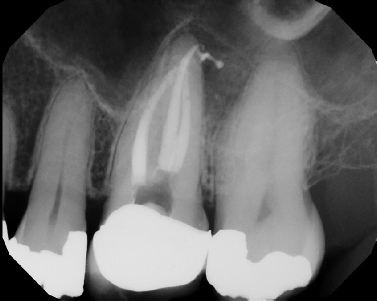

Root Canal Retreatment - Meriden 8 mos. recall Post-op Pre-op